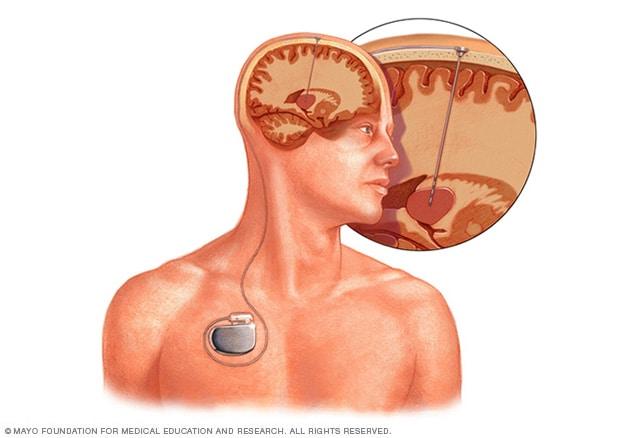

In vagus nerve stimulation, a device placed under the skin of the chest stimulates the vagus nerve in the neck. This sends signals to the brain that lessen seizures.

Deep brain stimulation involves putting electrodes deep within the brain. The impulses from the electrodes help the body manage the brain activity that causes seizures. The electrodes attach to a pacemakerlike device placed under the skin of the chest. The device manages how much stimulation happens.

• Vagus nerve stimulation. A device placed underneath the skin of your chest stimulates the vagus nerve in your neck. This sends signals to your brain that stop seizures. With vagus nerve stimulation, you may still need to take medicine, but you may be able to lower the dose.

• Deep brain stimulation. For this therapy, a surgeon implants electrodes within certain areas of the brain. The electrodes produce electrical impulses that regulate brain activity. The electrodes attach to a pacemaker-like device placed under the skin of your chest. This device controls the amount of stimulation produced.